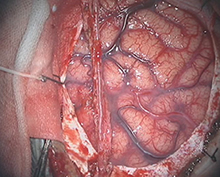

<実際の手術所見>

<手術中の脳血管撮影画像>

瘤(こぶ)は消失

患者様は術前からあった左視力低下以外に神経症状なし。元気に自宅退院された。